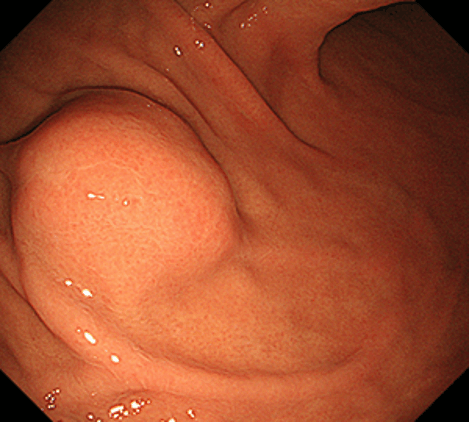

胃上皮下病変とは、胃の上皮(粘膜表層)の下の粘膜固有層(粘膜深層)や粘膜下層、固有筋層などに由来する腫瘤の総称です。以前は粘膜下層と固有筋層に局在する消化管間質腫瘍(GIST)、神経鞘腫、平滑筋腫、脂肪腫、迷入膵などを総称して粘膜下腫瘍(SMT)とすることが多かったのですが、近年は胃神経内分泌腫瘍などの、粘膜下層よりも浅層の粘膜固有層に主座を置く病変なども含めて、上皮下病変(SEL)とするのが一般的となりつつあります。本項では、従来のSMTに相当する病変について解説していきます。胃神経内分泌腫瘍については、別項をご参照ください。